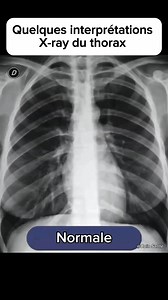

🚨Quelques interprétations de la radiographie du thorax. | Coin Santé plus

222.7K views

9 months ago